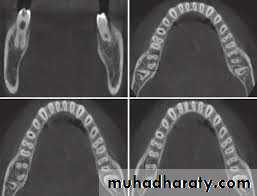

• Cone Beam Computed Tomography.

• Cone beam computed tomography (CBCT) produces three dimensional volumetric images that can be reliably measured. A major advantage of CBCT imaging is that all extraneous structures that would otherwise obscure the desired view can be excluded. This allows visualization of dimensions for the wanted structures.

cone beam computed tomography CBCT